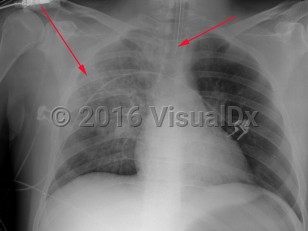

Staphylococcus aureus in responsible for about 1%-10% of community-acquired pneumonias and 20–30% of hospital-acquired pneumonias. Staphylococcus aureus pneumonia may result from air-borne contamination or aspiration or hematogenous seeding of the lungs from bacteremia or right-sided endocarditis. There may be a history of recent viral or influenzal illness. The clinical manifestations of staphylococcal pneumonia are similar to other causes of pneumonia except for a tendency to cause necrotizing infection with tissue destruction and cavitation. The patient will present with an abrupt onset of fever, tachypnea, pleuritic chest pain, and a productive cough with purulent sputum, which can be blood-tinged. Staphylococcus aureus is also one of the most common causes of empyema. In cases with accompanying endocarditis, stigmata-like subungual hemorrhages, murmur of aortic, tricuspid or mitral regurgitation, palmar Janeway lesions, and digital Osler nodes may be found.